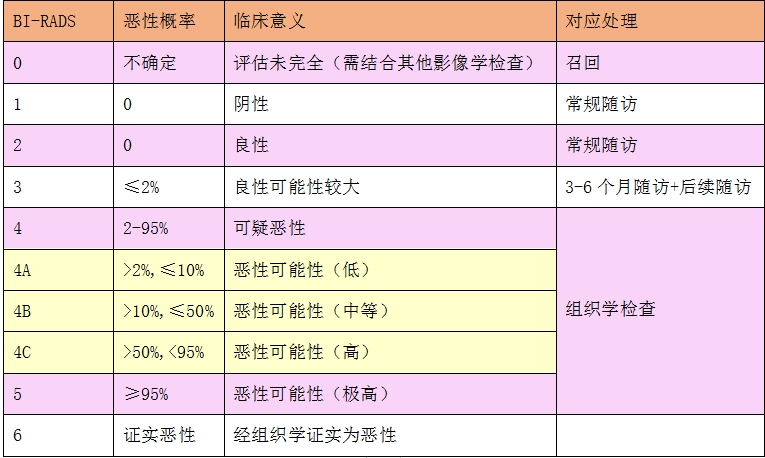

乳腺X线报告上看到的BI-RADS分类,是采用美国放射学会制定的乳腺影像报告和数据系统(Breast Imaging Reporting and Data System,BI-RADS)对乳腺X线所示的乳腺病变进行分类、评估。

乳腺X线检查BI-RADS分类解读如下图:

所以,对于像本文中李女士那样,乳腺检查报告中分类是BI-RADS 3的乳腺病灶(结节或钙化等),只需要定期复查就可以了。